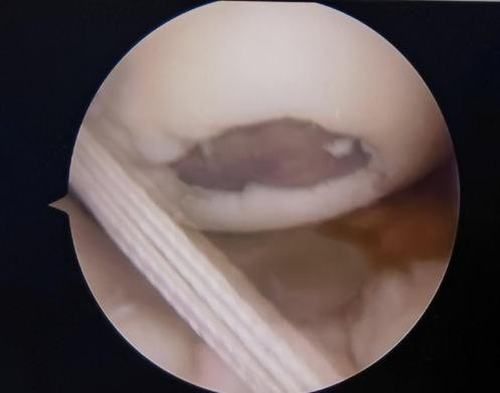

關節鏡下軟骨損傷

經患者同意后,李鵬主任手術團隊制定詳細手術方案。手術如期進行,經團隊密切配合,對幾位患者分別順利完成關節鏡下膝關節鏡鏡檢、關節清理、股薄肌半腱肌取腱移植術、前交叉韌帶重建術、軟骨損傷微骨折術、半月板縫合修整術等。

鏡下重建前交叉韌帶走形、張力良好